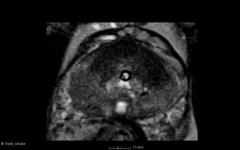

We are developing registration module in Slicer version 4 (which is using ITKv4) for deformable registration of prostate MRI.

Registration is applied to align preprocedural and intraoperational MR T2 image volumes. We are using masks the prostate for both image data sets. Registration is done using MMI metric with rigid, affine and B-spline stages applied in sequence. In Slicer3/BRAINSFit we use gradient descent for rigid/affine, and LBFGS for B-spline.